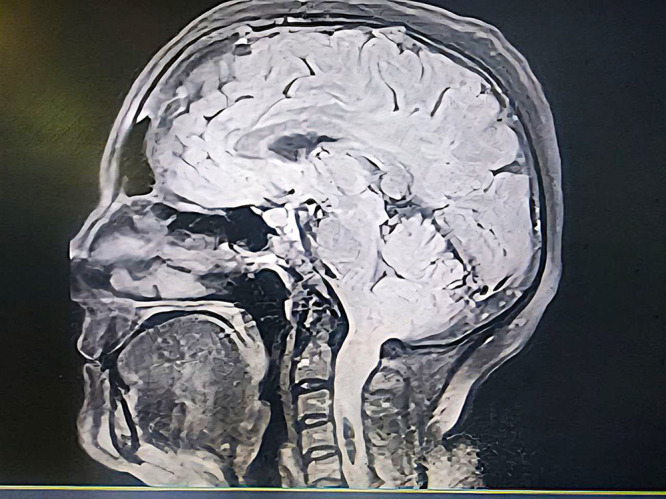

Background: Arnold-Chiari Malformation Type I (ACM-I) is a congenital disorder that can lead to severe neurological symptoms. While decompression surgery is the standard treatment, postoperative complications such as cerebrospinal fluid (CSF) leakage and infections can result in critical outcomes. Here, we report a case of septic shock following decompression surgery in a patient with ACM-I, emphasizing the challenges in postoperative critical care management.

Case presentation: A 45-year-old woman with rheumatoid arthritis and progressive neurological symptoms underwent decompression surgery for ACM-I. On postoperative day five, CSF leakage was noted at the surgical site, accompanied by fever and leukocytosis. Despite broad-spectrum antibiotics, the patient developed septic shock, requiring mechanical ventilation and vasopressor support. CSF cultures revealed Acinetobacter baumannii infection, necessitating surgical debridement and intrathecal colistin. Despite aggressive management, the patient succumbed to septic shock.